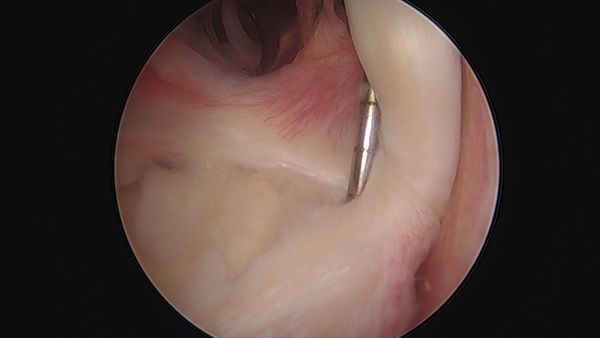

The normal sublabral sulcus ranges from approximately 3-5 mm and may increase with age. Therefore, if the sublabral sulcus is increased and associated with exposed bone (bare sublabral footprint), this is indicative of detachment of the superior labrum from the superior glenoid. It is particularly relevant, since the superior aspect of the glenoid under the labrum (the normal sublabral sulcus) is normally covered with articular cartilage (arthroscopic figure), a bare sublabral footprint with exposed bone (further supported by associated undersurface labral fraying) is again indicative of detachment of the superior labrum from the glenoid. When this detachment is significant, stability of the biceps root may be affected and the tendon may be easily translated medially and laterally with a probe (Figure 11).

Testing of SLAP Lesion

Figure 11. SLAP lesion tested arthroscopically. Reproduced from XX with permission.

Finally, dynamic stability of the superior labrum and biceps root is evaluated by placing the arm in the functional throwing position of 90 degrees of abduction and full external rotation. In patients with an intact superior labrum the biceps root and superior labrum remain centered on the superior glenoid and the intra-articular portion of the biceps tendon merely changes its angular position to the superior labrum. However, in patients with tears of the superior labrum (particularly, if involving the posterior superior labrum), as the arm is brought into external rotation, the torsional force from the biceps tendon lifts the superior labrum off the glenoid and the labrum begins to “peel-back” off the glenoid and falls off medially. This is the "peel-back" sign that indicates an unstable superior labrum.